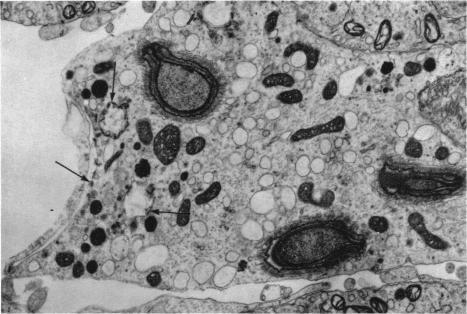

Proceedings of the anatomical society of great britain and ireland; proceedings of the anatomical society of australia and new zealand.

J Anat. 1966 Oct;100(Pt 4):921-50.

17103500

https://pmc.ncbi.nlm.nih.gov/articles/PMC1270849/